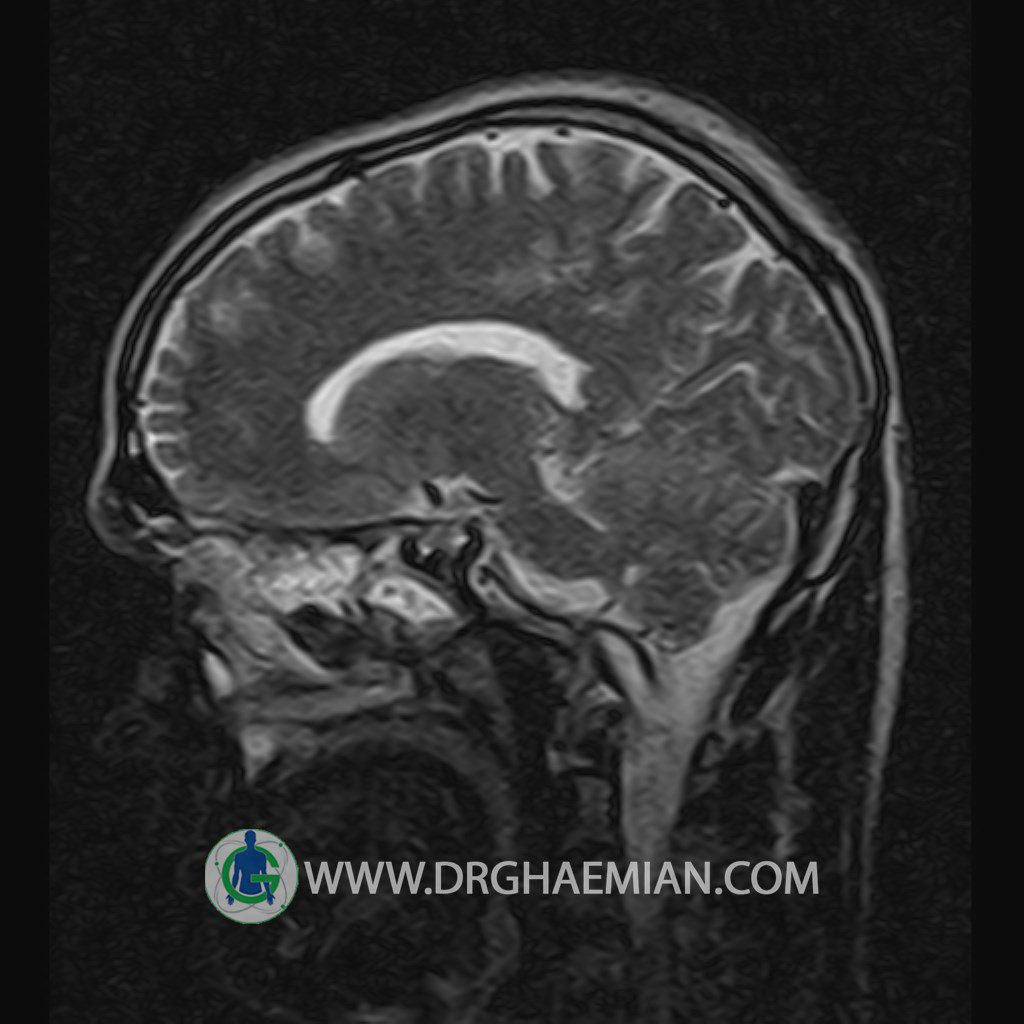

پزشکان اغلب از تصویربرداری ام آر آی برای تشخیص و درمان عارضه های پزشکی که فقط با استفاده از اشعه ایکس یا میدان مغناطیسی و امواج رادیویی قابل مشاهده است، استفاده می کنند. دستگاه ام آر آی تصاویر دقیق از ساختار های داخلی بدن ایجاد می کند. در این کیس یک میکروآدنوم در هیپوفیز بیمار مشاهده می شود.

HYPOPHYSIS MRI

(with and without contrast)

Technique: Axial , coronal T1 , Axial , coronal , sagittal T2 , Axial, coronal T1 post Gd & 64 dynamic thin coronal slices.

REPORT :

– Small hypoenhancing mass lesion ( 3 x 4 mm ) in posterior of pituitary stalk suggestive for micro adenoma

– Mucosal thickening in ethmoid & maxillary sinuses

is seen